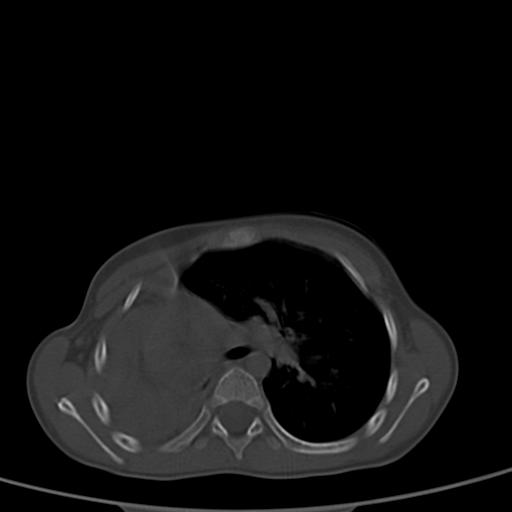

患儿,女,5岁,平素活动后气短,左侧面瘫.右侧胸廓较左侧塌陷.

两侧胸廓不甚对称,左侧稍膨隆,右肺体积明显变小,密度增高,未见正常通气肺组织,纵隔结构明显右移,心脏边缘欠清,外形似增大。纵隔血管间隙不清晰,左肺外形增大,部分肺组织突向右侧胸腔,左肺内未见异常密度影,右侧支气管逐渐变细,其内未见异常密度影。右侧未见叶及段支气管。右侧膈肌升高。

1。右肺体积小(考虑右肺发育不全)

2。左肺代偿性增大

3。心影增大?